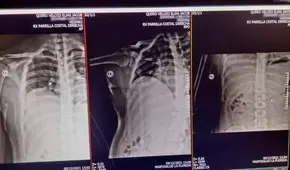

En 2019, las protestas en Chile, que empezaron como una protesta contra el alza en el precio del boleto de metro y derivaron en un clamor por un modelo económico más justo y derechos sociales, ocasionaron una treintena de muertos y miles de heridos, entre ellos muchos con traumas oculares. Conocido como el 18-O, cada año se conmemora el aniversario de las masivas manifestaciones en el país sudamericano.